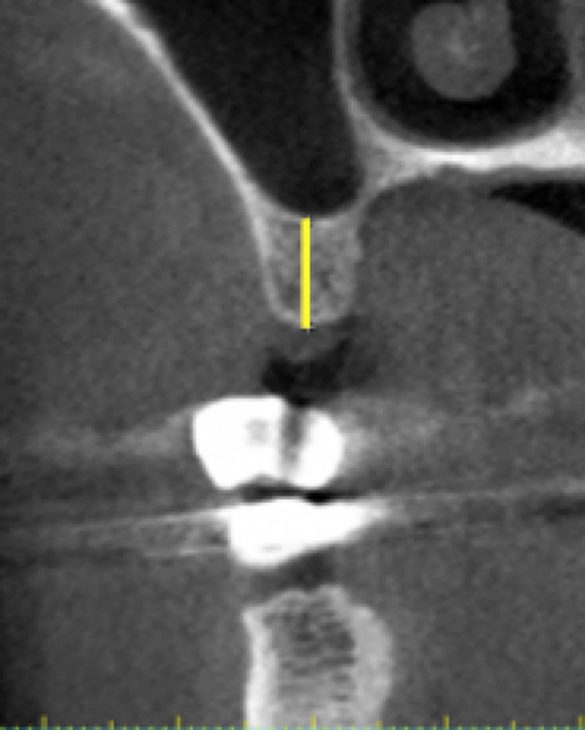

Măsurătorile din scanarea CBCT au fost înregistrate pe secțiunea transversală. O linie dreaptă perpendiculară pe o tangentă la creastă a fost extinsă până la podeaua sinusului maxilar. S-a măsurat lungimea liniei și s-a notat ca „înălțimea crestei CBCT” (fig. 1, 2). Măsurătorile periapicale ale aceleiași zone au fost înregistrate prin extinderea unei linii drepte paralele cu axul lung al dintelui natural sau implantului adiacent, de la creasta alveolară până la podeaua sinusului maxilar. Lungimea liniei a fost măsurată și înregistrată ca „înălțimea crestei PA” (fig. 3).

De asemenea, orientarea setărilor planului de referință au un impact asupra măsurătorilor liniare.18 Acest lucru poate fi vizualizat în fig. 10, care prezintă un exemplu pentru diferite măsurători liniare obținute cu o setare a planului de referință cu +/- 12°. În prezentul studiu, s-a verificat setarea planului de referință, pentru a avea linia secțiunii transversale paralelă cu dintele adiacent, așa cum se vede în fig. 1-3.